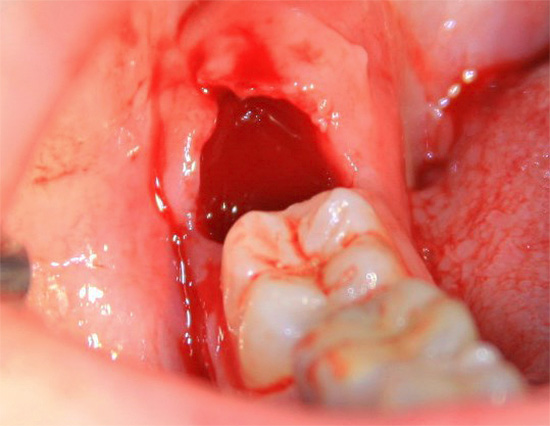

Como o orifício parece normal após a extração do dente

Após a extração do dente, o sangramento do orifício geralmente ocorre imediatamente (mas às vezes a adrenalina do anestésico estreita os vasos tanto que o orifício está quase “seco” no início e o sangramento se desenvolve apenas mais tarde quando o paciente já está em casa). Normalmente, o sangue para dentro de 3-30 minutos, formando um coágulo no buraco, que protege a ferida de influências externas adversas.

A foto abaixo mostra como o buraco fica logo após a remoção do dente do siso, anteriormente escondido sob a gengiva: